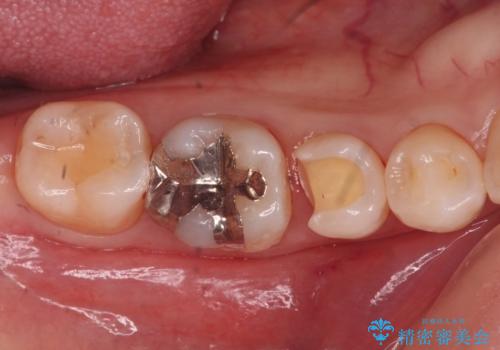

銀の詰め物を白くしたい。

- 銀が目立つのがやだとの事で来院。

二つとも一緒に治療可能だが、まずは一箇所とのご希望だったので

一つずつ治療を行うことにしました。

銀の詰め物を外し、拡大鏡で虫歯がないか確認してe-maxインレーで治療をしました。